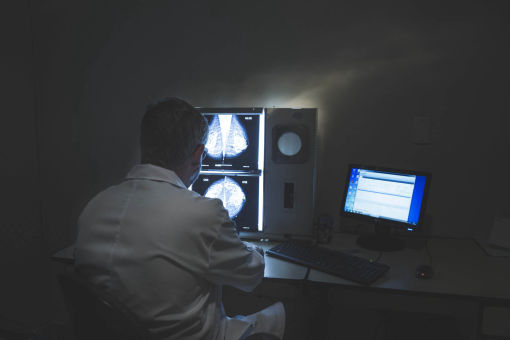

Busca pela melhor imagem

Corpo clínico formado pelos profissionais mais experientes

Atendimento humanizado, exclusivo e personalizado

Somente com excelência em imagem, experiência profissional e atendimento exemplar é possível sustentar 25 anos de história como uma das melhores opções da Baixada Santista.

Mamografia bilateral

Mamografia com compressão localizada

Mamografia com magnificação